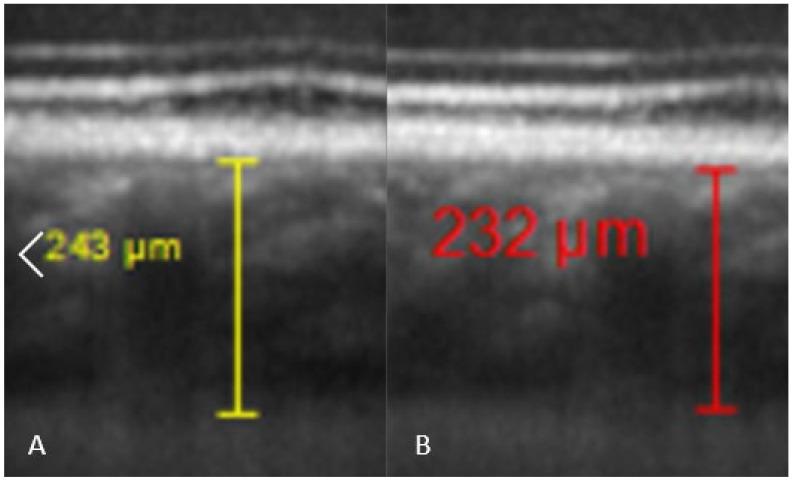

Background and Objective: Several cases of central serous chorioretinopathy (CSC) in divers have been reported in our medical retina center over the past few years. This study was designed to evaluate possible changes induced by SCUBA diving in ophthalmic parameters and especially subfoveal choroidal thickness (SFCT), since the choroid seems to play a crucial role in physiopathology of CSC. Materials and Methods: Intraocular pressure (IOP), SFCT, pachymetry, flow-mediated dilation (FMD), blood pressure, and heart rate were measured in 15 healthy volunteer divers before diving, 30 and 60 min after a standard deep dive of 25 m depth for 25 min in a dedicated diving pool (NEMO 33). Results: SFCT reduces significantly to 96.63 ± 13.89% of pre-dive values (p = 0.016) 30 min after diving. It recovers after 60 min reaching control values. IOP decreases to 88.05 ± 10.04% of pre-dive value at 30 min, then increases to 91.42 ± 10.35% of its pre-dive value (both p < 0.0001). Pachymetry shows a slight variation, but is significantly increased to 101.63 ± 1.01% (p = 0.0159) of the pre-dive value, and returns to control level after 60 min. FMD pre-dive was 107 ± 6.7% (p < 0.0001), but post-dive showed a diminished increase to 103 ± 6.5% (p = 0.0132). The pre-post difference was significant (p = 0.03). Conclusion: Endothelial dysfunction leading to arterial stiffness after diving may explain the reduced SFCT observed, but SCUBA diving seems to have miscellaneous consequences on eye parameters. Despite this clear influence on SFCT, no clear relationship between CSC and SCUBA diving can be drawn.

潜水后 30 分钟,SFCT 显著降低至潜水前的 96.63 ± 13.89%(p = 0.016)。60 分钟后恢复至对照值。IOP 在潜水后 30 分钟降至潜水前的 88.05 ± 10.04%,然后升高至潜水前的 91.42 ± 10.35%(均 p < 0.0001)。角膜厚度略有变化,但显著升高至潜水前的 101.63 ± 1.01%(p = 0.0159),60 分钟后恢复至对照水平。FMD 潜水前为 107 ± 6.7%(p < 0.0001),但潜水后增加至 103 ± 6.5%(p = 0.0132)。前后差值有统计学意义(p = 0.03)。